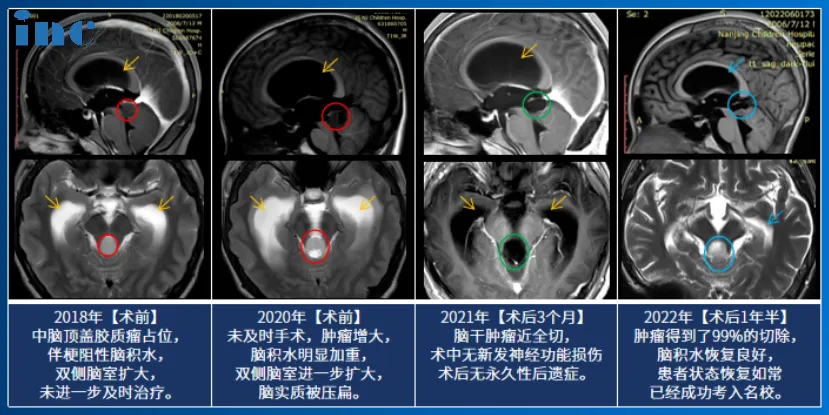

脑干胶质瘤保守治疗2年肿瘤压扁大脑,巴教授术后1年考上名校

14岁的小永查出脑干胶质瘤,影像片子显示:脑干-中脑顶盖,伴有幕上脑室扩张积水,脑室及大脑实质已经受压变形。在与患者家属沟通中我们得知,小永2018年就出现过轻微头痛、头晕,去医院检查发现脑干肿瘤,并伴有梗阻性脑积水。小永的父亲咨询了很多知名专家。“每次都说毛细胞星形细胞瘤一般不长,观察就行,但是后来我最后一次去找他们的时候,我说症状太重,不行就做手术,他们最后和我说实话,因为做手术风险过大,所以说建议你观察……”这一拖就是2年多,孩子的病情越来越严重。

巴教授仔细研究小永的相关资料后表示:“已经有很明显的手术指征。我想知道为什么他还没有得到治疗,因为病变是从2018年就知道了。无论如何,我强烈建议不要给病人提供脑室腹腔分流术,因为这样一来,他将一直依赖于这个分流术。”小永的父母觉得再不能拖下去了,经过反复考量后,开始准备带孩子去德国找巴教授做手术,在INC协调和帮助下迅速办完手续,不到一个月的时间内到达德国做上了手术。

手术结果令人欣喜,小永的肿瘤得到近全切除,病理结果为毛细胞型星形细胞瘤,这是一种预后较好的胶质瘤,全切或近全切后复发率非常低。

2022年7月,术后已经过了1年半,我们对小永进行随访时得知他已经凭借优秀的中考成绩,考入示范高中,其中体育成绩还获得了满分,完全看不出来曾经做过开颅脑干手术。